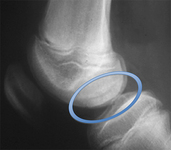

Osteochondral lesion of medial talus

From the collection of H. Chambers, MD